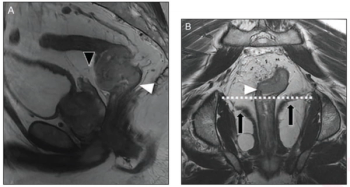

Noting a rapidly changing paradigm for the treatment of rectal cancers, the authors of a new literature review discuss current and emerging principles in MRI assessment and staging.